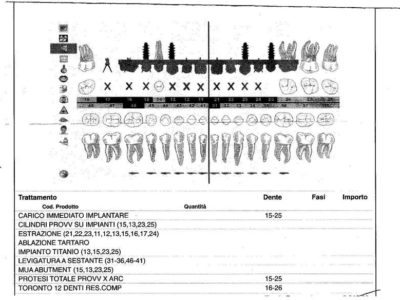

Grazie alla completa informatizzazione dello studio, è possibile comunicare con il proprio medico in formato elettronico. Con l’invio di documentazione varia, rapporti medici, radiografie e fotografie attraverso posta elettronica, per richiedere un’opinione medica e la valutazione approssimativa delle spese dei trattamenti necessari, vengono resi possibili anche senza un incontro diretto con il medico.